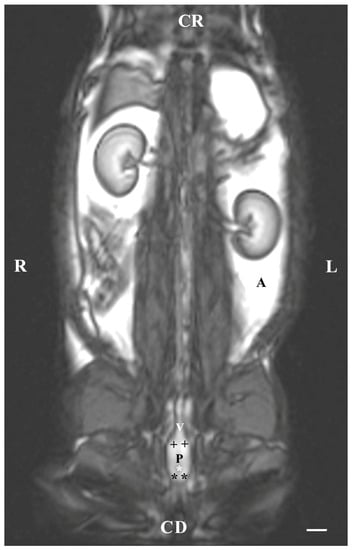

Dorsal imaging in the pelvis (at the greatest distance, dorsal to the pelvic symphysis) on T1-weighted sequences demonstrated the bulbourethral glands as homogeneous findings with low or intermediate intensity similar to that of the urethra. The intensity of the adipose tissue was used as a relative marker for the degree of tissue intensity in the studied subjects. The hypo-intense character of the glandular findings was defined as the relatively high intensity of the prostate complex and the penile root. The shape of the studied glands was oval, but their borders (capsule) were not sufficiently defined. The glands were located lateral to the caudal part of the pelvic urethra, caudal to the prostate complex and cranial to the root of the penis (Figure 4).

Figure 4. T1-weighted dorsal image of rabbit pelvis (at the level to the greatest distance, dorsal to the pelvic symphysis): R—right; L—left; CR—cranial; CD—caudal. Bulbourethral glands (white horizontal arrows), prostate gland complex (P), the pelvic part of the urethra (white star), root of the penis (black stars), and adipose tissue (A). Line—10 mm.

On the dorsal imaging of glands in T1-weighted sequences, at a relatively middle distance dorsal to the pelvic symphysis, the glandular findings could clearly be defined by the hypo-intense part of the pelvic urethra (ventromedial) and the neck of the urinary bladder (cranial). The bulbourethral glands were located caudal to the prostate complex and dorsolateral to the pelvic part of the urethra. Their shape was oval. The intensity of the bulbourethral glands was the lowest compared to that of the prostate complex. The image of the vesicular glands had the highest intensity compared to other accessory sex glands (Figure 5).

Figure 5. T1-weighted dorsal image of rabbit pelvis (at the level of the middle distance, dorsal to the pelvic symphysis): R—right; L—left. CR—cranial; CD—caudal. Bulbourethral glands (black stars), prostate complex (P), vesicular glands (black cross), the pelvic part of the urethra (white star), neck of the urinary bladder (V), and adipose tissue (A). Line—10 mm.

The dorsal imaging of the pelvic findings was on T2-weighted sequences but at the closest distance to the pelvic symphysis, which demonstrated the ventral parts of the bulbourethral glands located on the lateral wall of the pelvic urethra. The latter were relatively hyperintense, homogeneous, with elongated craniocaudally soft tissue structures, compared to the vesicular glands and the prostate glandular complex. The pelvic urethra was hypo-intense compared to the ventral parts of the bulbourethral glands, prostate complex and vesicular glands. The shape of the ventral parts of the bulbourethral glands was craniocaudally elongated and oval, with poorly defined borders (capsule). The glandular finding was visualized as a compacted, thickened and hyper-intense part of the urethral wall (Figure 6).

Figure 6. T2-weighted dorsal image of rabbit pelvis (at the level, close to the pelvic symphysis): R—right; L—left; CR-cranial; CD—caudal. Bulbourethral glands (horizontal white arrows), prostate complex (P), vesicular glands (white cross), pelvic symphysis (S), neck of the urinary bladder (V), the pelvic part of the urethra (white star), urinary bladder (U), adipose tissue (A). Line—10 mm.

The T2-weighted dorsal image of the bulbourethral glands at the pelvic symphysis demonstrated the ventral portions of the glandular findings to be hyper-intense and homogeneous compared to the cranially located ventrocaudal parts of the prostate complex and pelvic urethra. The glands were presented as tissue-defined, irregularly oval perineal structures located at the caudal end of the pelvic urethra and cranially from the beginning of the penis. The studied glands were found in the central part of the perineum, with a characteristic intensity that could distinguish them significantly from the close soft tissues in the perineal region (Figure 7).

Figure 7. T2-weighted dorsal image of rabbit pelvis (at a greater distance, at the level to the pelvic symphysis): R—right; L—left; CR—cranial; CD—caudal. Bulbourethral glands (black stars), caudal part of the prostate gland complex (white horizontal arrows), the pelvic part of the urethra (white star), urinary bladder (U), and penis (P). Line—10 mm.